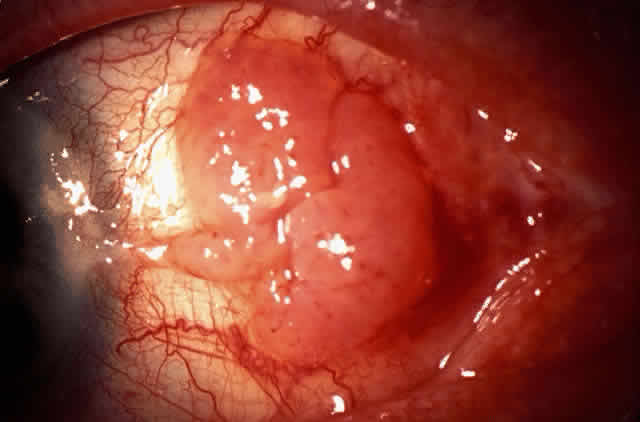

In the conjunctiva, HPV can induce papillomatous lesions (papillomas and inverted papillomas) and epithelial dysplastic lesions consisting of conjunctival intraepithelial neoplasia and squamous cell carcinoma. Conjunctival papillomas were traditionally divided into infectious, limbal, and inverted types; however, current data suggest that all types have a viral etiology. All sites of the conjunctiva can be affected, and involvement of the contiguous epithelium of the lacrimal canaliculus, lacrimal sac, and nasolacrimal duct has been noted to occur.38,61,62 Conjunctival papillomas can be pedunculated or sessile and are typically shiny, flesh-colored, and papillomatous (Fig. 1). Each papillary frond has a vascular core that is easily seen through the nonkeratinized epithelium. The papillomatosis is responsible for the typical appearance of evenly spaced vessels throughout the lesion. If keratinized, these lesions may appear whitish and dull. Papillomas can be either unilateral or bilateral, and they can be either solitary or multifocal (Fig. 2). Inverted papillomas are the least common type of papilloma in all sites, but they constitute a larger portion of lacrimal sac tumors than other periocular tumors.63,64

Fig. 1. Solitary conjunctival papilloma in fornix of immunocompetent man.

Fig. 2. Confluent conjunctival papillomata in patient with multiple recurrent lesions and chronic immunosuppression after multiple renal transplants.